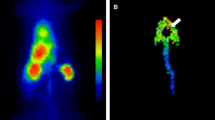

Myocardial perfusion SPECT

Myocardial perfusion SPECT was performed using a rotating dual-detector gamma camera with the detectors mounted at right angles and fitted with high-resolution collimators (Vertex; ADAC Laboratories, Milpitas, CA, USA). Data acquisition was started 30 min after the injection of 740 MBq 99mTc-tetrofosmin at rest. The image acquisition variables included the following: a 140-keV photopeak with a 20% window, 64 projections at 40 s/projection over a 180°(90°/detector) elliptical orbit, a 38-cm roving detector mask, and a matrix size of 64×64. Acquisitions were gated for eight frames in a cardiac cycle.

The eight-interval projection data sets were prefiltered with a 2D Butterworth filter (order 2.5, critical frequency 0.22 cycles/pixel, pixel size 0.64 cm) and reconstructed with filtered backprojection using a ramp filter; no attenuation correction was performed. The resliced transaxial image sets were reoriented into short-axis sets that were then processed in the batch mode using a stand-alone workstation running automatic LVEF quantification software. The projection data sets were also summed and prefiltered with a 2D Butterworth filter (order 2.5, critical frequency 0.33 cycles/pixel, pixel size 0.64 cm), producing high-count short, vertical, and horizontal long-axis images for qualitative interpretation and for polar plot and circumferential count displays.

The LV myocardium was automatically divided into 20 segments according to quantitative perfusion SPECT (QPS) software (AutoQUANT; ADAC Lab., CA, USA). The most basal six segments and two apical regions were excluded from analysis. The average values of two regions in the septal and lateral segments corresponding to the segments on the FDG scan were calculated. A total of eight segments, comprising four basal and four apical segments, were used for analysis. The percentages of myocardial flow (%Flow) of these eight segments were calculated using the values of QPS software.